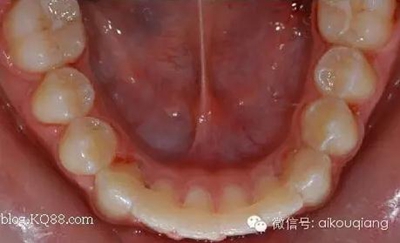

其實(shí)還有一種我們也經(jīng)常采用的固定保持器,效果不錯,除了黏結(jié)有點(diǎn)麻煩外,其實(shí)也是不錯的選擇!